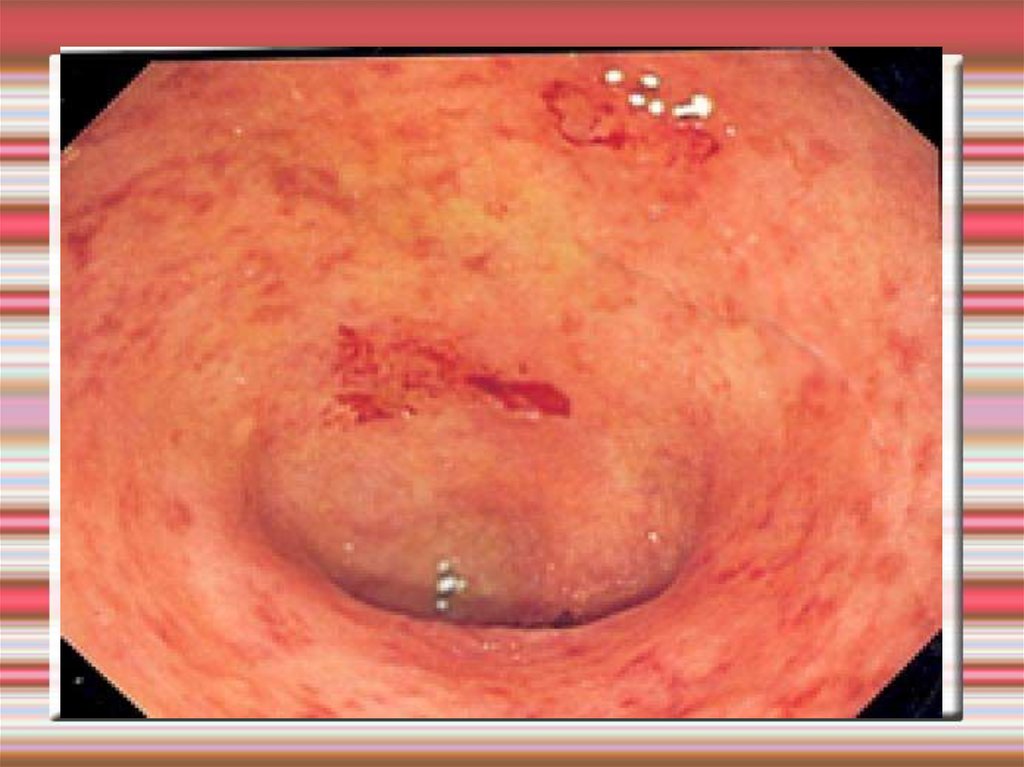

Кровотечение из дивертикула

19. Кровотечение из дивертикула